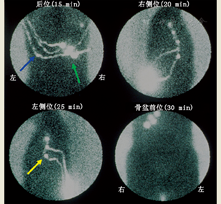

3.显像。在黑色素瘤中,根据原发肿瘤的位置,显像必须包括所有可能引流的部位。如果原发肿瘤位于患者的躯干部位,不仅要做左右侧腋窝和颈区显像,也要做左右侧骨盆和腹股沟区显像(图1)。对于肢体肿瘤,上肢部位应做肘前区和腋窝显像,下肢部位应做腹股沟和腘窝区显像。对于头颈部鳞状细胞癌,显像范围应包括整个头颈部,尤其是肿瘤近端的所有部位,因该区域淋巴引流通常流向下方。同样,对于头颈部SLN,操作者应时刻铭记头颈部有很多微小而致命的结构(如颈动脉窦等,切忌随意按摩)。躯干和头颈部注射后越过身体中线的对侧引流很常见(图2)[16]。此外,对于某些适应证(如观察膈面引流),SPECT或SPECT/CT或许是首选。

(3)透射成像。可使用泛源(99Tcm 或57Co)获得患者的平面像。此时获得的图像既包括发射数据(来自患者体内的放射性药物),也包括透射数据(来自泛源)。此类图像有身体轮廓(图2),为所示SLN提供了解剖参考。